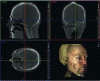

Made for a large technical public, this article wants to deliver key-elements required for the comprehension of dental and maxillo-facial radiology, from the intraoral 2D one to the recent 3D imaging.

The intra- and extra-oral dental radiological examinations described here are considered to be first-line when they are minimally invasive and easy to perform in the office. If necessary, volumetric imaging can be used as a second line of defence, as it is less energy-efficient in terms of radiation but provides a wealth of three-dimensional information, and is becoming increasingly important for complex treatment plans. The recent arrival, spectacularly rapid spread and technical evolution of CBCT have had a major impact on dental practice, to the extent that new indications (HAS), new codes (CCAM) and appropriate training have become essential. What's more, indications that used to involve CT scans are now being redirected towards CBCT, thereby limiting patient dose.

Based on the initial and ongoing training provided by the Dental Radiology Department at the Paris Descartes Faculty of Dental Surgery, this article aims to provide the key elements needed to understand the practice of radiological imaging in dental and maxillofacial surgery, from 2D intra-oral radiology to recent volume imaging. It is on the basis of the necessary dialogue between the world of engineering sciences...